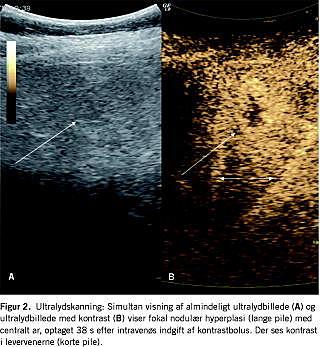

Ultralydundersøgelse af abdomen blev gennemført hos 23 patienter (Figur 2 ). I elleve tilfælde fandt man en hypo- til isoekkoisk proces. I fem skanninger var processen hyperekkoisk, og i fire skanningsbeskrivelse blev ekkoforholdene ikke angivet. I tre tilfælde var det ikke lykkedes at synliggøre FNH-læsionen ved ultralydundersøgelse, men ved supplerende billeddiagnostik. I ingen af tilfældene blev diagnosen FNH stillet.

Seksten patienter blev undersøgt med flere billeddiagnostiske modaliteter. Langt størstedelen fik primært foretaget ultralydundersøgelse af abdomen. Almindelig ultralydundersøgelse har høj sensitivitet, men ringe specificitet [14], kan vise lokalisation og størrelse og muliggør samtidig bioptering, hvilket gør det muligt at sikre diagnosen. FNH er af flere årsager vanskellig at skelne fra maligne tumorer billeddiagnostisk [14]. For eksempel kan det fibrolamellære hepatocellulære karcinom danne et centralt ar og dermed minde om FNH [15]. Endvidere findes FNH i atypiske varianter, som kan være uden centralt ar og uden karakteristisk arterieforsyning [16]. I dette studie blev der dog ikke fundet nogen atypiske varianter.

Fokale processer i leveren kan karakteriseres dynamisk med CT, MR- eller ultralydskanninger efter intravenøs administration af en bolus af et relevant kontrastmiddel. Dermed opnås højere specificitet og sensitivitet [17]. Kontrastopladningen i FNH kan vise den typiske arterielle forsyning og det centrale ar. Påvises FNH ved to uafhængige billeddiagnostiske undersøgelser, vil biopsi kunne udelades. Biopsi anbefales dog fortsat ved atypisk billeddiagnostik eller ved klinisk mistanke om malignitet. I dette studie var kun to MR-undersøgelser diagnostiske af alle de billeddiagnostiske undersøgelser, og i begge tilfælde valgte man alligevel at bioptere.